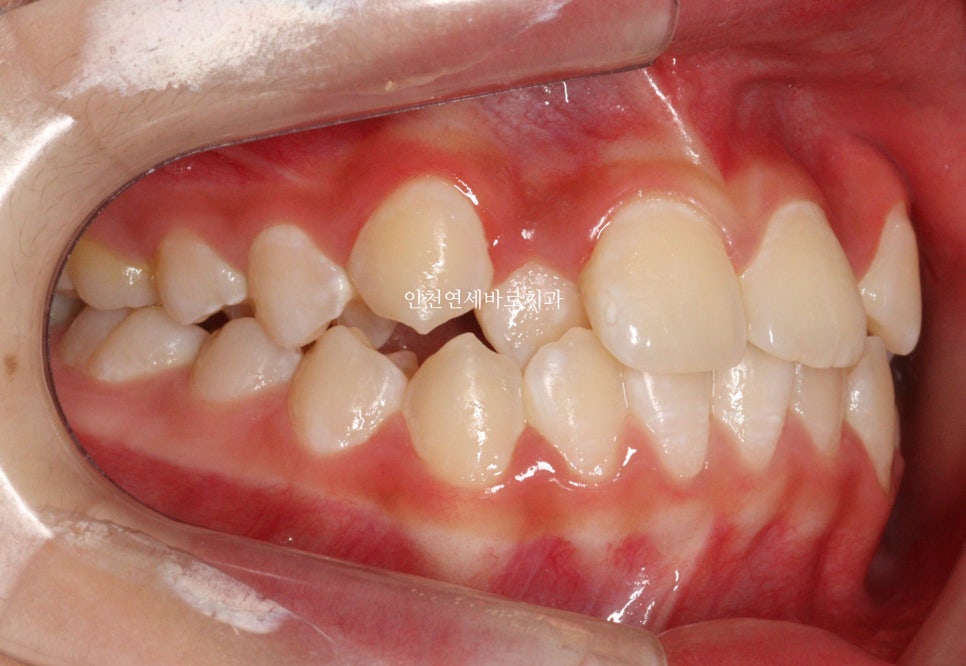

두번째 치아가 덧니로 있는 경우의 치료는 흔한 경우지만

생각보다 많은 노하우가 필요한 치료라고 생각합니다.

교정 치료 중에 화살표 최후방 치아가 맹출하여,

이 치아를 배열하는 과정에서 치료가 조금 더 길어지긴 했습니다